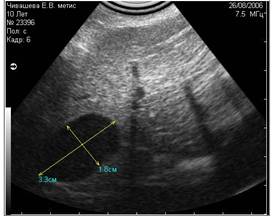

Рис. 8. На снимке представлен гиперэхогенный объект в полости мочевого пузыря, испускающий эхоакустическую тень. На основании этого артефакта, мы можем предположить, что этот объект является конкрементом. |

Рис. 9. На снимке представлен похожий по величине и эхогенности объект в полости мочевого пузыря, не испускающий эхоакустической тени. На основании этого признака, мы можем предположить, что изучаемый объект является новообразованием. |